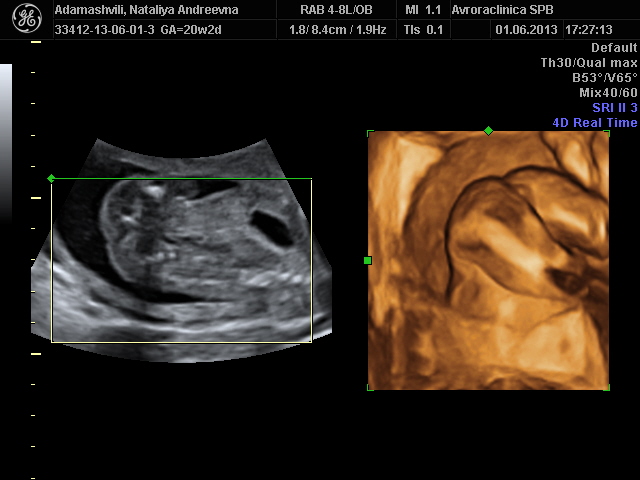

Срок 20нед 1 день

Спасибо за пожелания!! Тут попка кверху торчит, ножки согнуты, это 3Д. 2Д сама плохо понимаю, вроде бочком лежит

Со стороны попки)